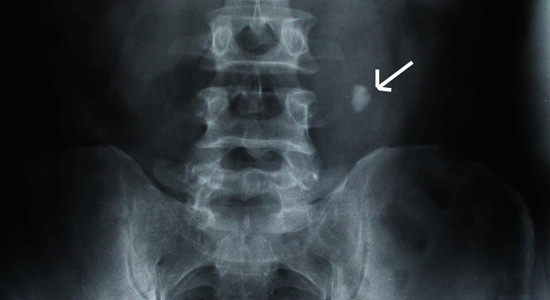

- рентгенография;

Камень в мочеточнике при рентгенографии

Диагностика уролитиаза у мужчин состоит из нескольких этапов, сопоставление результатов которых, позволяет с большой точностью определить не только наличие камней, но и их конфигурацию, структуру и размер.